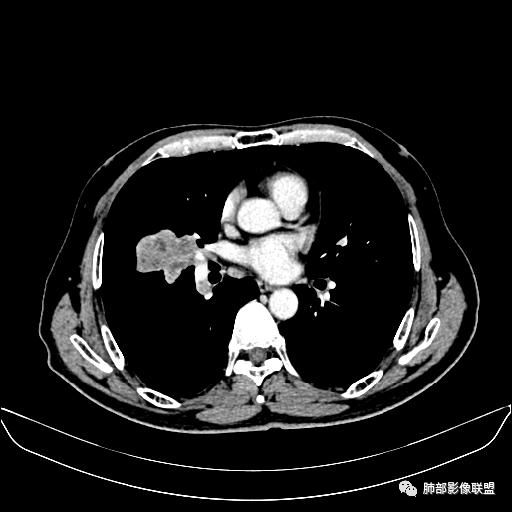

静脉期

老年男性,因“咳嗽咳痰1月余。”入院。病程中咳嗽咳痰,咳黄白痰,间断咯少许鲜红色痰血。PPD阳性。胸CT:右肺中叶外侧段支气管管腔阻塞,大片实性病变,病灶边缘光滑,部分边缘膨隆,可见分叶,肺门及纵隔可见肿大淋巴结,并可见钙化。增强可见病灶明显强化,而且延迟强化明显,病灶内多发低密度区,内见血管影,血管变细、部分血管破坏。考虑恶性病变可能性大,鉴别慢性肉芽肿性病变。

胸CT:跨叶大肿块,主体在中叶,右中叶外侧段支气管阻塞,病灶部分边缘膨隆,可见分叶,部分边缘平直,肺门及纵隔可见肿大淋巴结。增强病灶不均匀强化,延迟强化明显,病灶内多发低密度区,内见血管飘浮,部分血管变细、模糊。考虑:恶性病变可能性大,大细胞?淋巴瘤?鉴别慢性肉芽肿性病变。

右肺中叶软组织肿块,外围向内生长,叶间胸膜向前内移位,肿块近肺门侧跨叶,中叶外侧段支气管截断,密度不均匀,双侧肺门及隆突下见肿大淋巴结,增强后呈中度不均质强化,肺动脉供血,多发坏死区,边界尚清,坏死区域内见结构,结合病史考虑恶性,鉴别诊断1结核,爬行征是沿支气管树分布,外宽,内窄,周围有卫星灶,内气管狭窄后扩张,此例沿叶间胸膜长轴分布,气管有截断,不典型。2炎性肉芽肿,符合的地方下方层面增强后延迟性轻度环形强化,不符临床无发热等急性感染病史,实验室指标不符,病灶周围渗出及慢性炎性改变有,不明显。

吴婧老师和南边老师都对该病例进行了深入分析。从支气管管壁的增厚,支气管狭窄后扩张,支气管粘液栓,病灶形态,到病灶不均匀强化及坏死彻底,到周边病灶及肺组织空气的潴留,加之纵隔内淋巴结肿大伴钙化等等,都支持慢性炎性病灶,尤其是结核。

墨西哥仙人掌征---结核        影像上结核灶,粗大的均匀枝干,推测是支气管囊状扩张引起的,在非支气管区,形成圆形坏死囊群;如果这些坏死比较稀薄,又遇到扩张支气管,就会形成粗大的“墨西哥仙人掌”。结核引起的支气管近端炎症纤维化,可以造成支气管阻塞,从而将干酪样坏死物封堵在管腔内。仙人掌主干内部应该是干酪为主,稀薄的,具有流动性,时间久了会出现钙化。

结核坏死与鳞癌鉴别有一点是结核坏死没有方向性,鳞癌有。鳞癌靠近支气管近端部分,血供容易维持,不易坏死,所以坏死靠外侧。而结核干酪样坏死,把一定体积的流动性坏死物,包裹起来,什么形状最省料?坏死物包裹,表面积最省的自然是圆球形,而遇到支气管,坏死物一多,就把支气管撑大了。包裹物是就地取材,扩张的支气管就成了包裹结构。